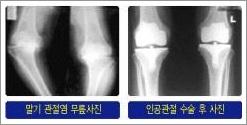

ÅðÇ༺ °üÀý¿°Àº °üÀýÀ» º¸È£ÇÏ´Â ±â´ÉÀ» ÇÏ´Â ¿¬°ñÀÌ ¼Õ»óµÇ°Å³ª ¶Ç´Â ÅðÇ༺ º¯È·Î ÀÎÇØ ¿¬°ñÀÌ ´â¾Æ ¾ø¾îÁö°í ±× ¹Ø¿¡ ÀÖ´Â »Àµµ ¼Õ»óµÇ¾î ±âÇüÀûÀ¸·Î »À°¡ ÀÚ¶ó³ª°Ô µÇ¸é¼ ½ÉÇÑ ÅëÁõÀÌ »ý±â´Â ÁúȯÀÔ´Ï´Ù.

¨ç ¿¢½º·¹ÀÌ »çÁø»ó ¹«¸¿¬°ñÀÌ ¸ðµÎ ´â¾Æ¼ »À¿Í »À°¡ ¸Â´êÀº °æ¿ì